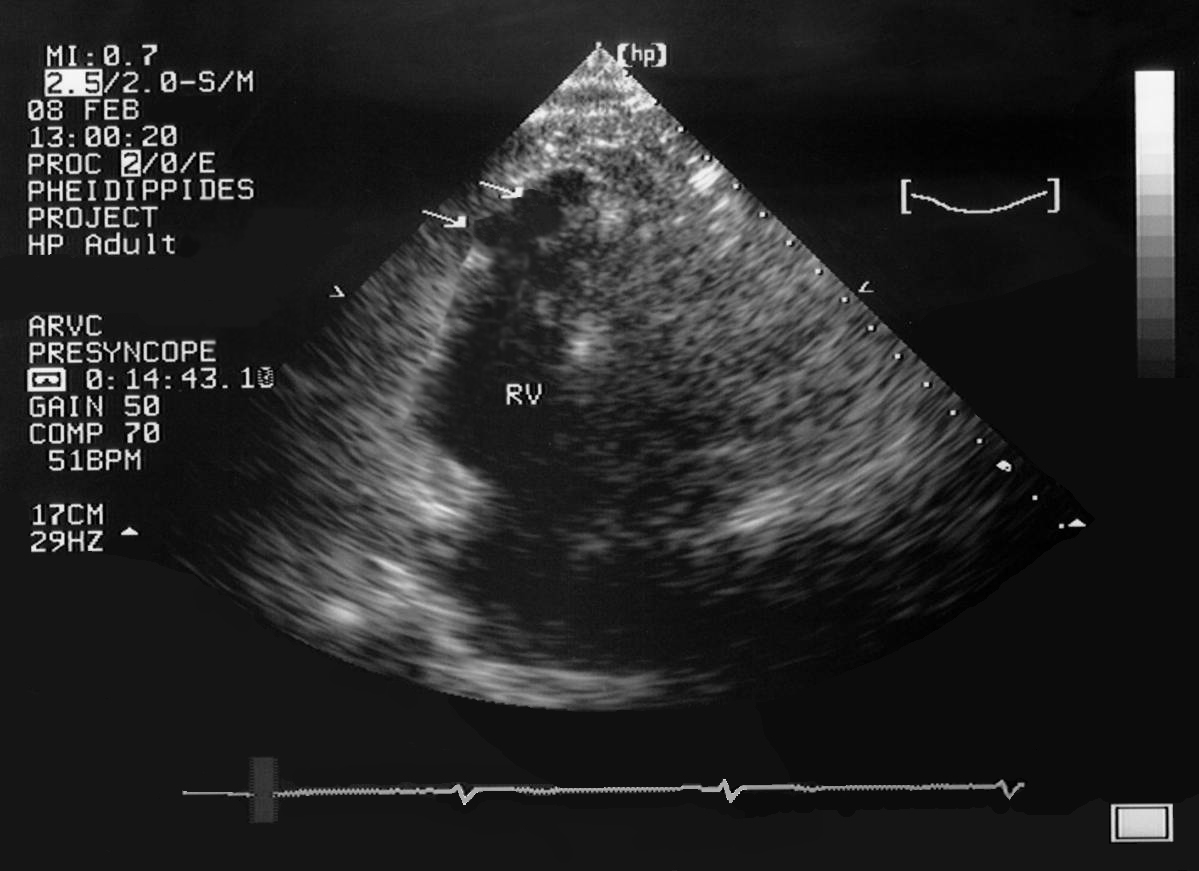

A 23-year-old female professional dancer died suddenly following physical activity. Routine postmortem examination failed to establish the cause of death. No cardiac structural abnormalities were revealed. She had a history of presyncopal episodes during the last two months preceding her sudden cardiac death (SCD). Following the proband’s death, her family was referred to our department for clinical evaluation. Following informed consent, family members were evaluated with a standard protocol. All individuals underwent detailed non-invasive evaluation followed by genetic testing.

The proband’s uncle was the first family member to undergo clinical investigation. He had been diagnosed with arrhythmogenic right ventricular cardiomyopathy/dysplasia (ARVC/D) almost 5 years before his niece’s SCD. The proband was positive for a plakophilin-2 (PKP2) mutation and both her father and uncle had a typical form of the ARVC/D disease. To strengthen our diagnostic assessment an immunohistochemical analysis was undertaken of a myocardial sample obtained at autopsy, which pointed towards ARVC. Thus, her death was attributed to ARVC. Probably, the mutation had been inherited from her paternal grandfather. Although he had never been clinically evaluated, and no tissue was available for genetic analysis, he had a history of SCD at the age of 72, thus, raising suspicions of cardiac diseaseDownloads